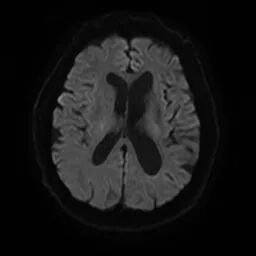

颅脑磁共振+头颈MRA:未见新发梗死;右侧颈内动脉C1段重度狭窄。

右侧颈内动脉C1段重度狭窄,引起右侧大脑半球的缺血,从而导致左侧肢体发作性无力等症状。

右侧桡动脉穿刺,置入7F薄壁鞘,造影示右侧颈内动脉C1段重度狭窄,狭窄率约90%,狭窄长度约22mm。通过加硬泥鳅导丝、125cm SIM2造影导管辅助,将5.5F Introsky X导管鞘置于右侧颈总动脉远端,选择KangFly微导丝携带Spider FX保护伞通过狭窄病变后释放保护伞,5.0*30mm球囊预扩张,置入9*40mm自膨式支架。